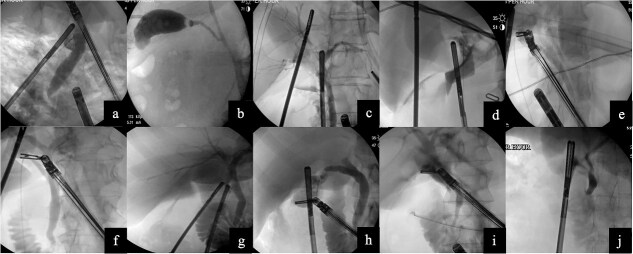

Indocyanine green fluorescent cholangiography (ICG) and intraoperative cholangiography (IOC) are both useful during cholecystectomy. Laparoscopic cholecystectomy with IOC is commonly performed in various situations; however, there have been concerns with performing IOC during robotic cholecystectomy such as operating room set up and increased operative time due to docking and undocking of the robot. We argue if IOC is readily available and is possible, safe, and not extremely time consuming, that it should be utilized in conjunction with indocyanine green fluorescent cholangiography, instead of preoperative magnetic resonance cholangiopancreatography (MRCP). This could potentially decrease overall cost and the hospital length of stay. We report our experience with ten cases and describe our operative technique.